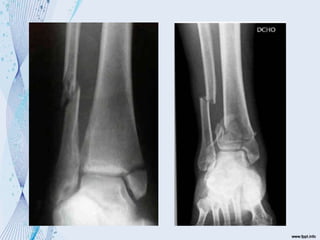

 Mecanismo de producción

Ruptura del ligamento lateral

externo

Avulsión del maléolo externo

Ruptura del LL + fx maléolo inter,

oblicua

Supinación – Aducción

Pronación - Abducción

Ruptura simple del ligamento interno o avulsión

del maléolo lateral y una fx transv del peroné

Fx peronea por arriba del ligamento tibioperoneo

interóseo

Pronación – rotación externa